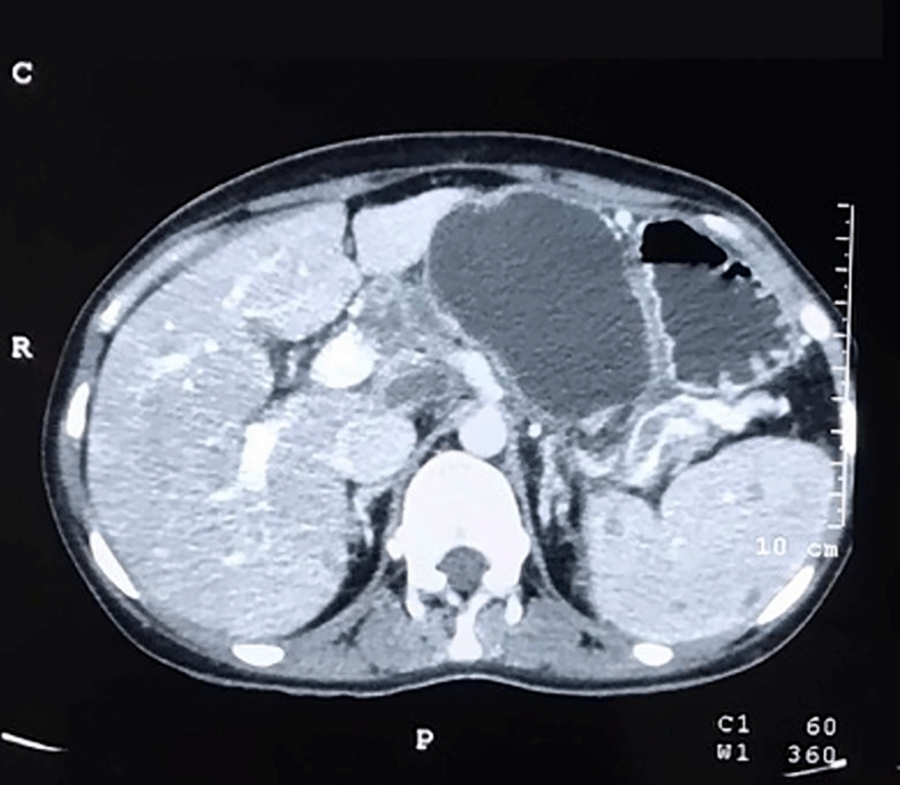

On evaluation, routine hemogram and biochemistry were within normal limits. Serum amylase and lipase were raised three times beyond normal. Pancreas protocol triphasic contrast-enhanced computed tomography (CECT) and contrast-enhanced magnetic resonance imaging (MRI) of the abdomen with cholangiopancreatography (MRCP) showed a large unilocular cystic lesion measuring 8.4 × 6.4 cm with non-enhancing thickened walls in the region of pancreatic neck and body (Figure 1). There was no evidence of calcifications, septations, or mural nodularity. Pancreatic parenchyma adjoining the cyst was atrophic, with some normally enhancing pancreas preserved near uncinate and tail regions. No peripancreatic fat stranding or post-inflammatory sequelae were noted. The main pancreatic duct (MPD) was prominent towards the tail, with no observed communication with the cyst (Figure 2). Multiple necrotic periportal and peripancreatic lymphadenopathy were also noted. A working diagnosis of pancreatitis, secondary to suspected cystic neoplasm of the pancreas, was made.

Figure 1. CECT Scan Axial Cuts Showing Large Cystic Lesion in Pancreatic Neck and Body. Published With Permission

Note. Thickened unenhanced walls and absence of mural nodularity.